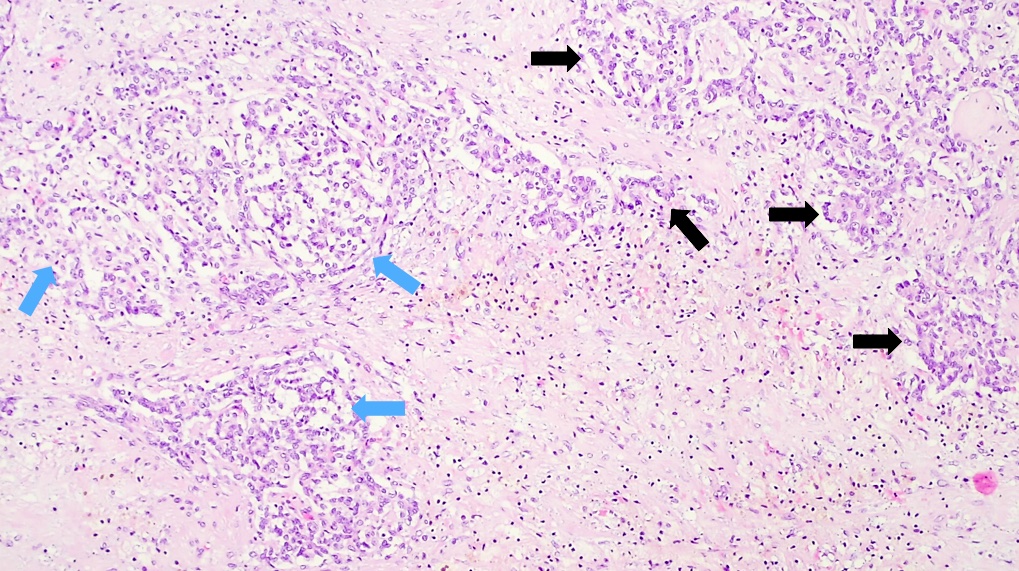

Microscopic (histologic) description

- Classified by the International Pediatric Liver Tumor Consensus Classification as epithelial or mixed epithelial and mesenchymal

- Epithelial hepatoblastoma may exhibit several patterns (alone or in combination): fetal, embryonal, small cell undifferentiated (SCUD), cholangioblastic and macrotrabecular (J Gastrointest Oncol 2018;9:326)

- Fetal pattern (Pediatr Dev Pathol 2020;23:79)

- Thin trabeculae or nests of small to medium sized cells resembling hepatocytes of the developing fetal liver

- Clear or finely granular cytoplasm with variable amount of glycogen and lipids

- Small round nucleus with indistinct nucleolus

- Foci of extramedullary hematopoiesis are usually present

- Typically has low mitotic activity, referred to as well differentiated hepatoblastoma

- A subset has increased mitotic activity, with decreased cytoplasmatic glycogen and pleomorphic nuclei, referred to as mitotically active hepatoblastoma

- Embryonal pattern (Pediatr Dev Pathol 2020;23:79)

- Resembles the developing liver at 6 - 8 weeks of gestation

- Solid nests or glandular / acinar morphology, with papillae and pseudorosettes

- Dark and granular cytoplasm without glycogen or lipids

- Enlarged nuclei with coarse chromatin, resembling blastemal cells

- Extramedullary hematopoiesis is usually absent

- Increased mitotic activity

- Mesenchymal pattern (Pediatr Dev Pathol 2020;23:79)

- Mature and immature fibrous tissue

- Osteoid or osteoid-like tissue (more abundant after chemotherapy)

- Hyaline cartilage

- Small subset may exhibit teratoid features: endodermal, neuroectodermal (neuronal cells, glial tissue, melanin producing cells) and complex tissue (striated muscle)

Microscopic (histologic) images